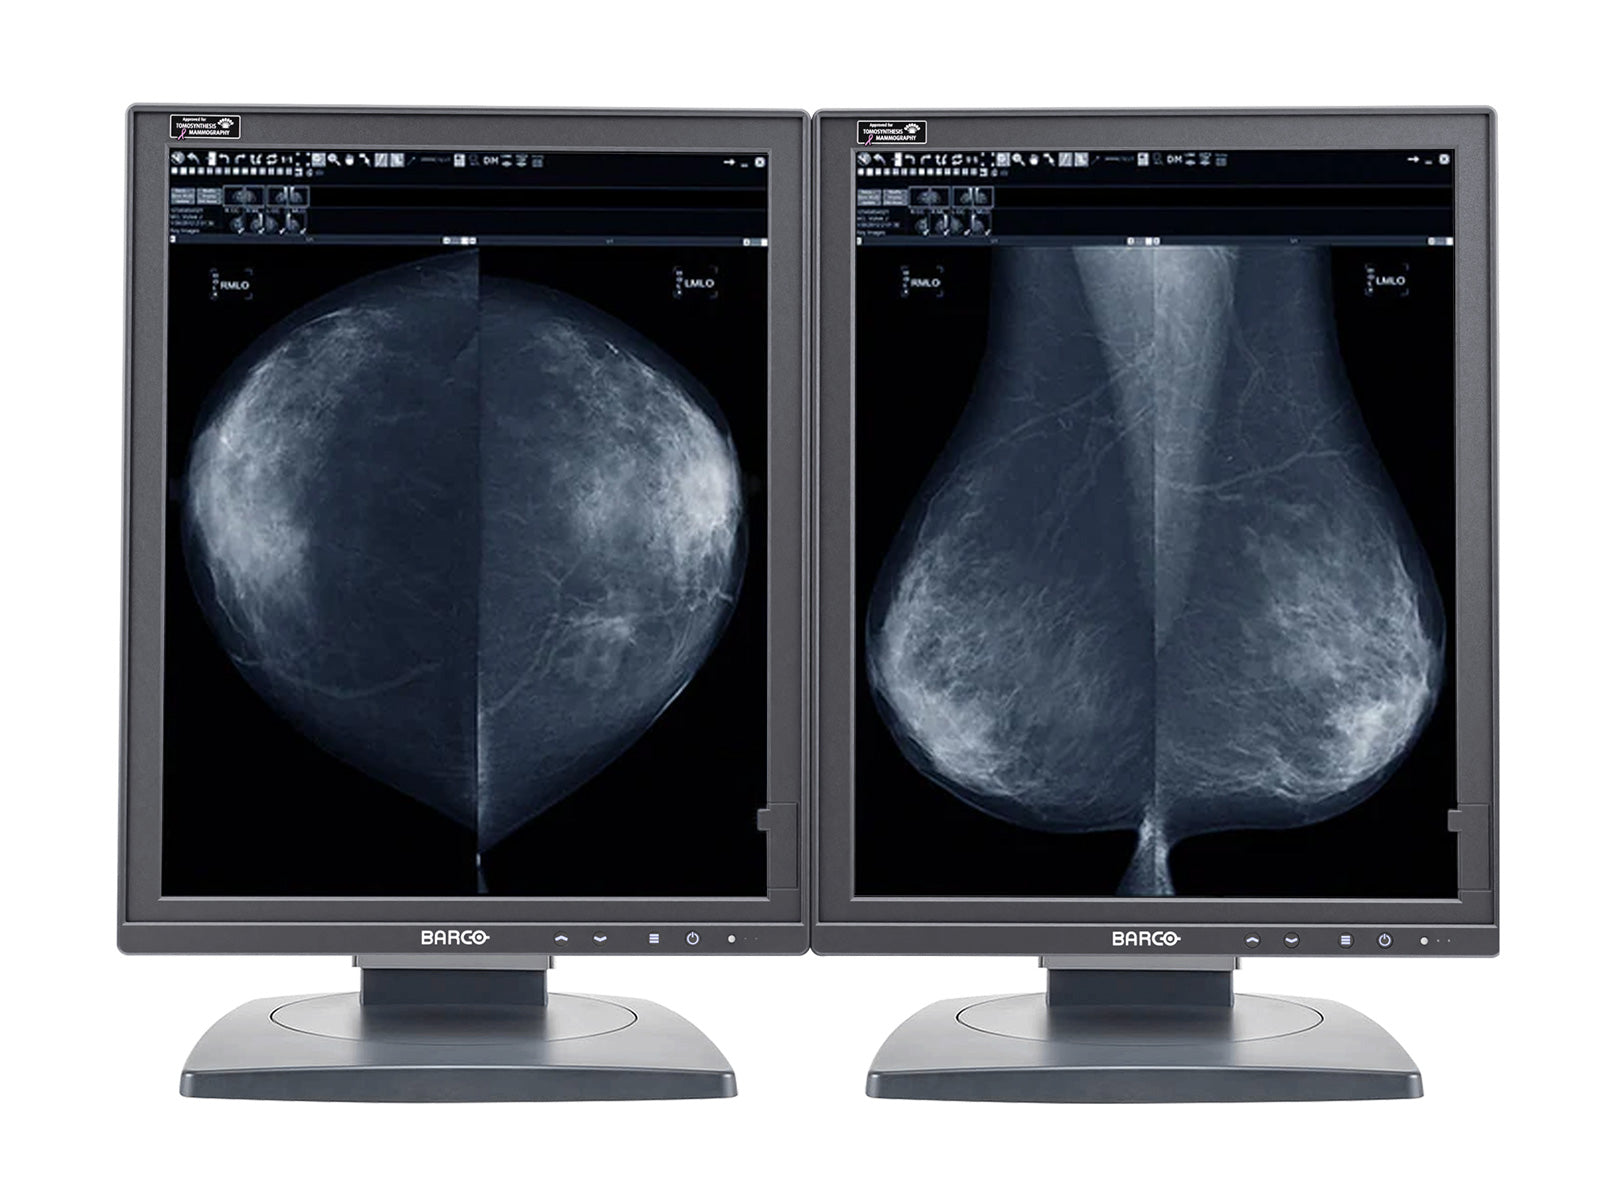

Barco Nio MDNG-5221 5MP 21" Grayscale LED 3D-DBT Mammography Breast Imaging PACS Display

Barco Coronis MDMG-5221 5MP 21" Grayscale Tomosynthesis 3D-DBT Mammography Display

Eizo RadiForce RX850 8MP 31" Fusion Color LED Mammo 3D-DBT Breast Imaging Display (RX850-BK)